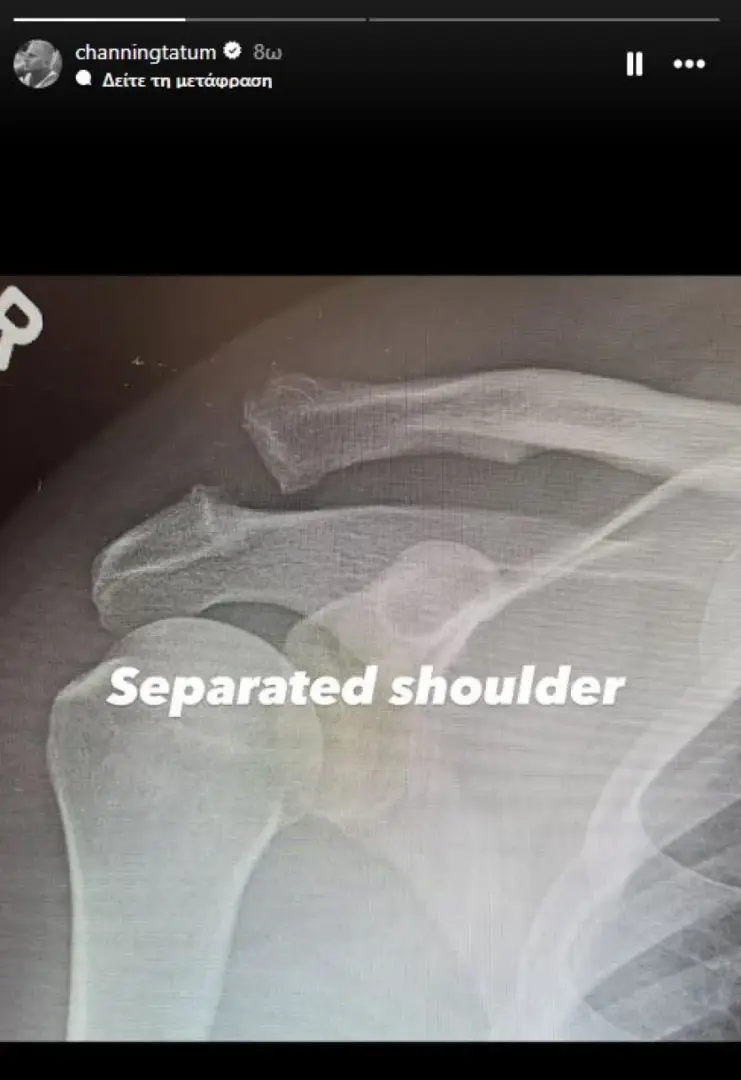

Ωστόσο, σε stories που έκανε στη συνέχεια, ο Τσάνινγκ Τέιτουμ αποκάλυψε ότι επρόκειτο για εξάρθρωση ώμου.

Ο ηθοποιός ανάρτησε μία φωτογραφία με ακτινογραφία του άνω βραχίονα και της περιοχής του ώμου, στην οποία φαινόταν ότι είχαν σπάσει δύο οστά. «Εξάρθρωση ώμου», σχολίασε. «Βιδωμένος ώμος. Γιούπι», ανέφερε στη λεζάντα της επόμενης ακτινογραφίας, στην οποία διακρίνεται πλέον μια μεγάλη βίδα που συγκρατεί τα οστά στη θέση τους.